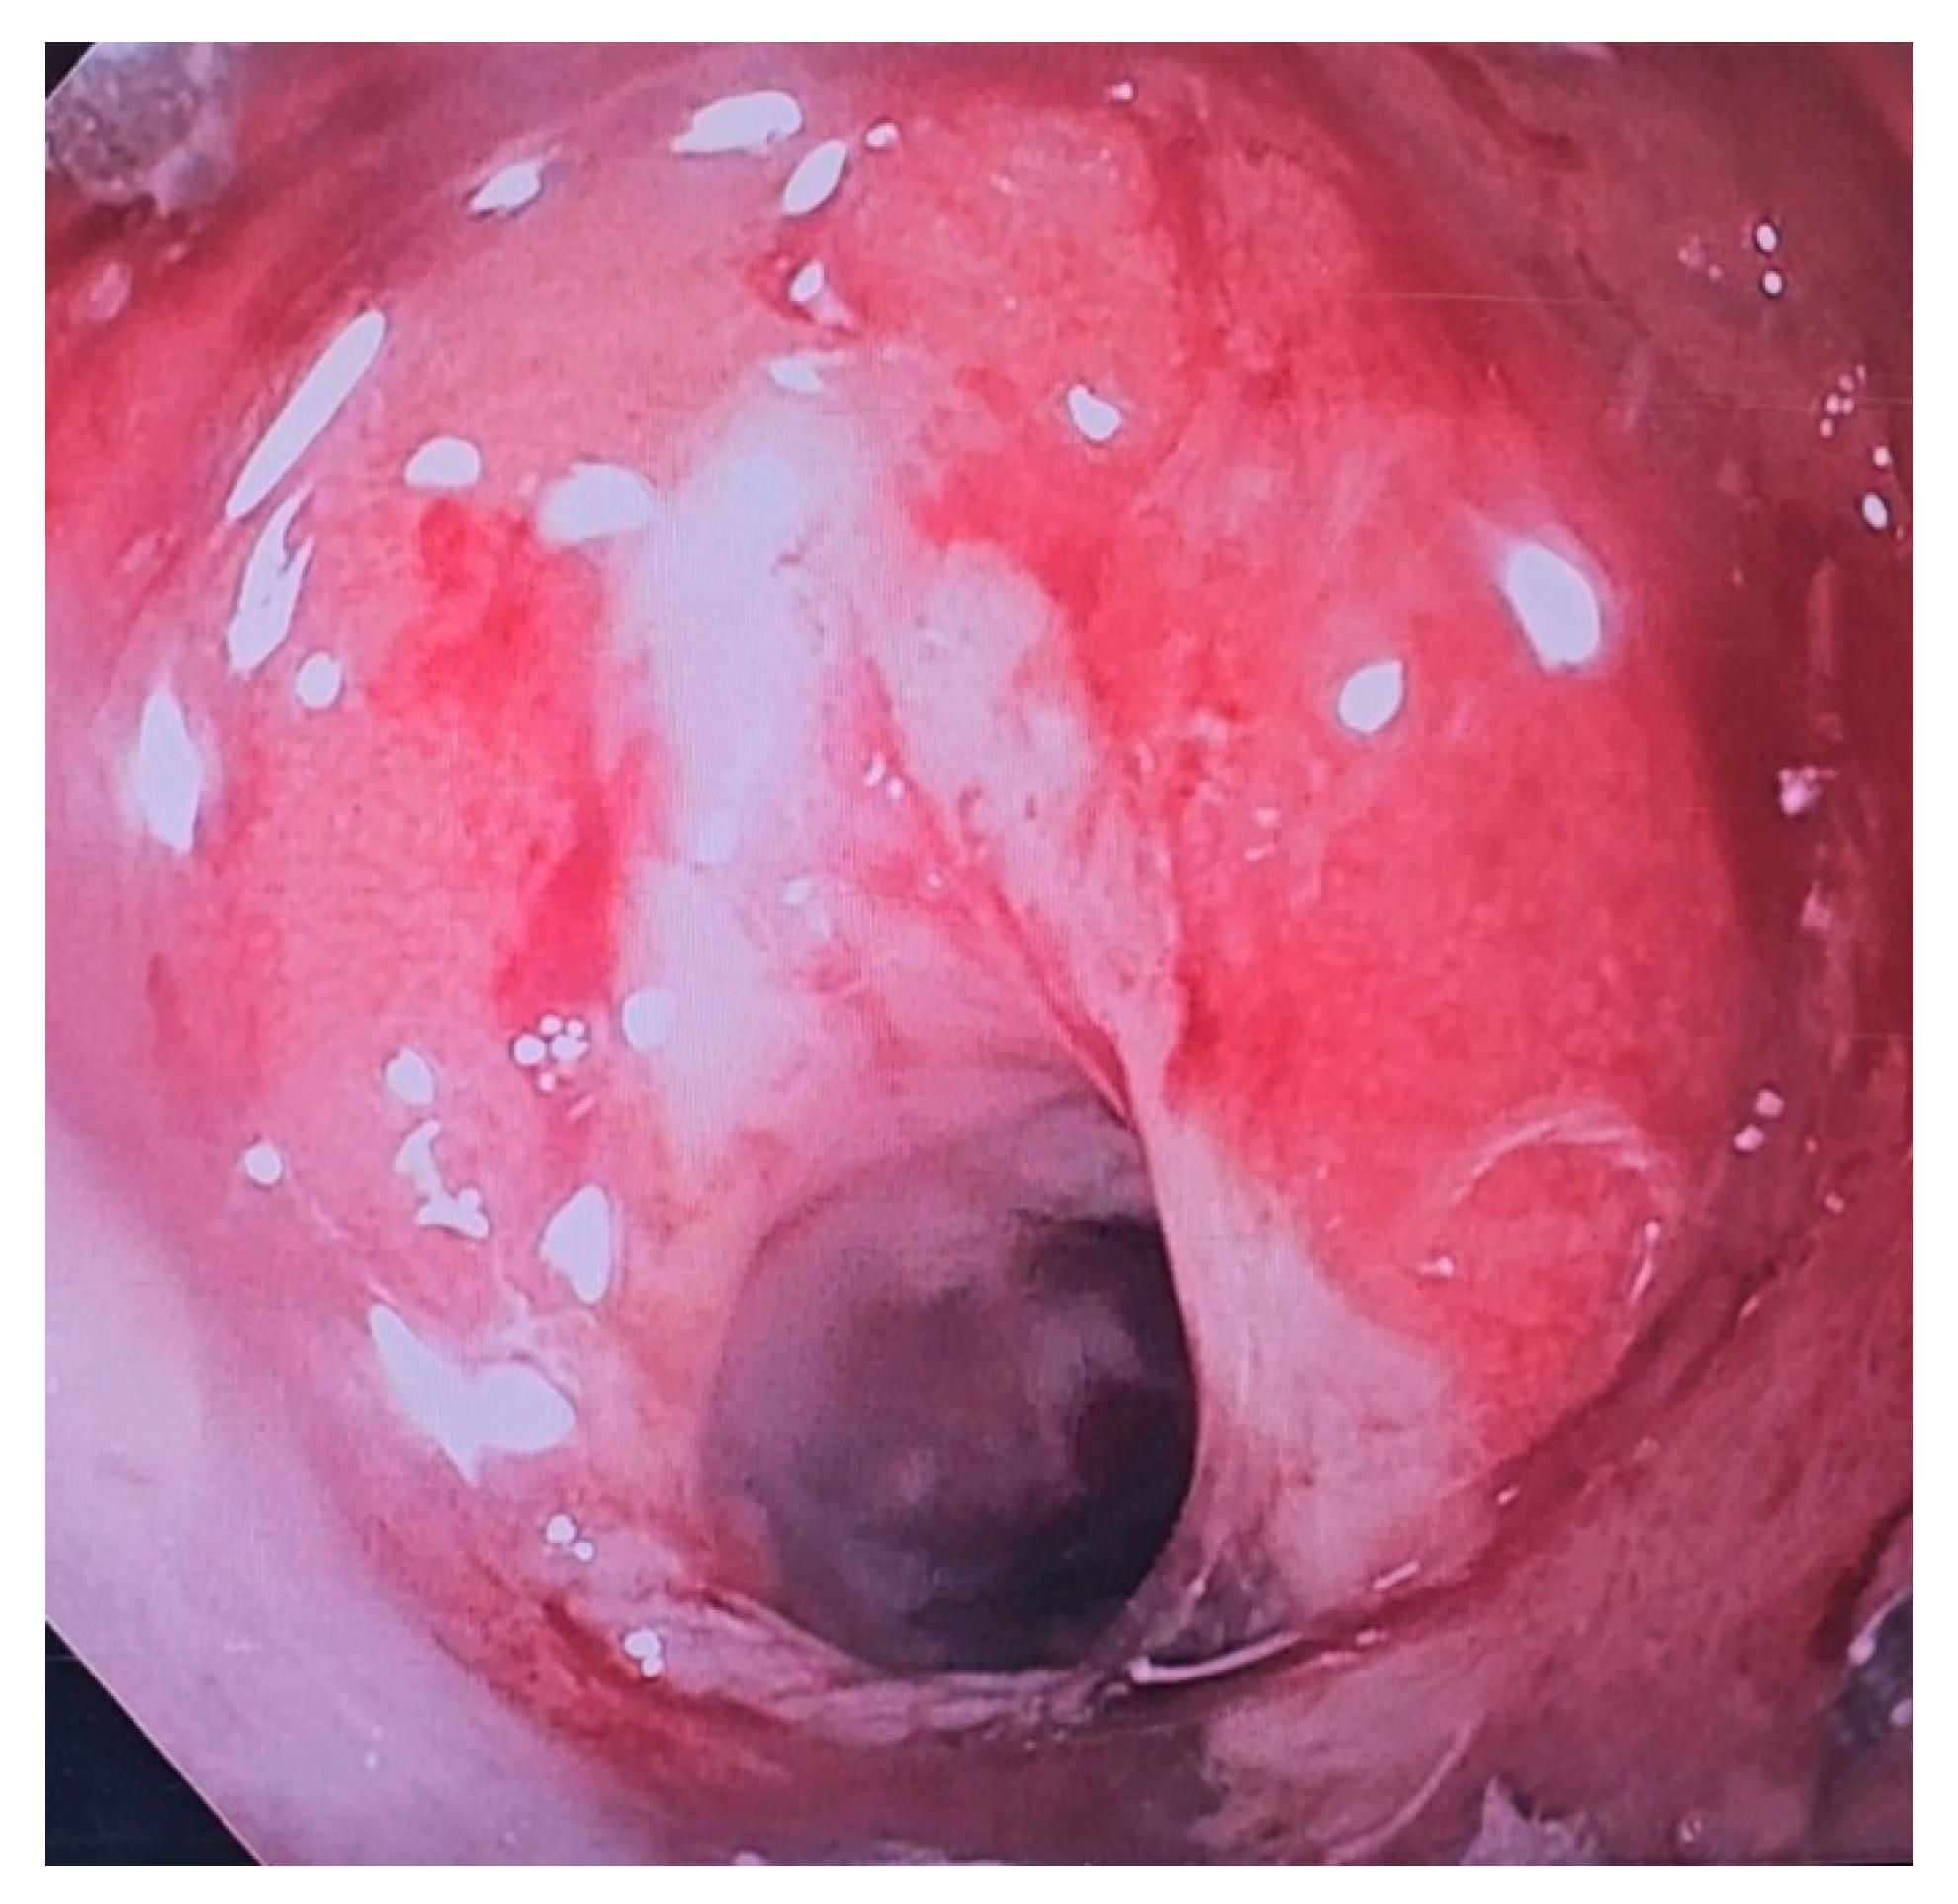

4. Endoscopic Vacuum Therapy (EVT)